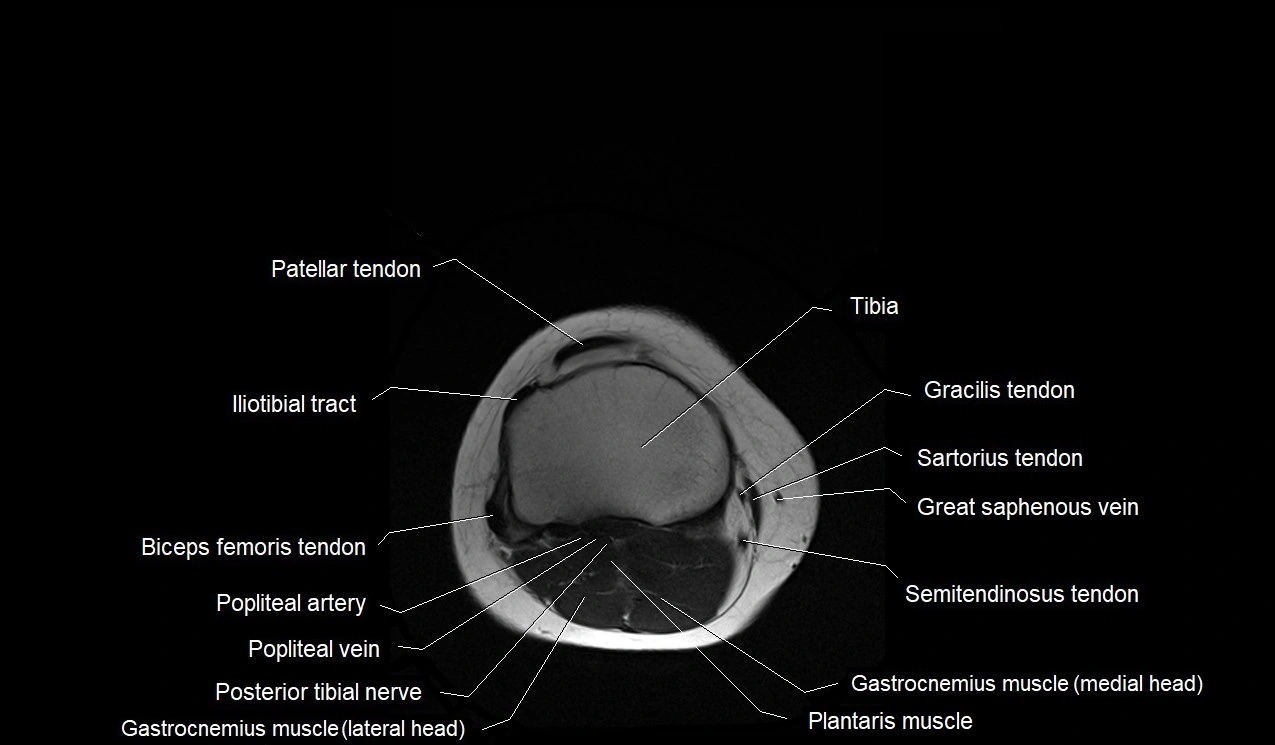

- Common fibular nerve

- Gastrocnemius muscle

- Gracilis tendon (Distal)

- Lateral gastrocnemius tendon

- Medial head of gastrocnemius muscle

- Patella

- Patellar tendon (patellar ligament)

- Plantaris muscle

- Popliteal artery

- Popliteal vein

- Sartorius tendon (Distal)

- Small saphenous vein

- Tibial nerve